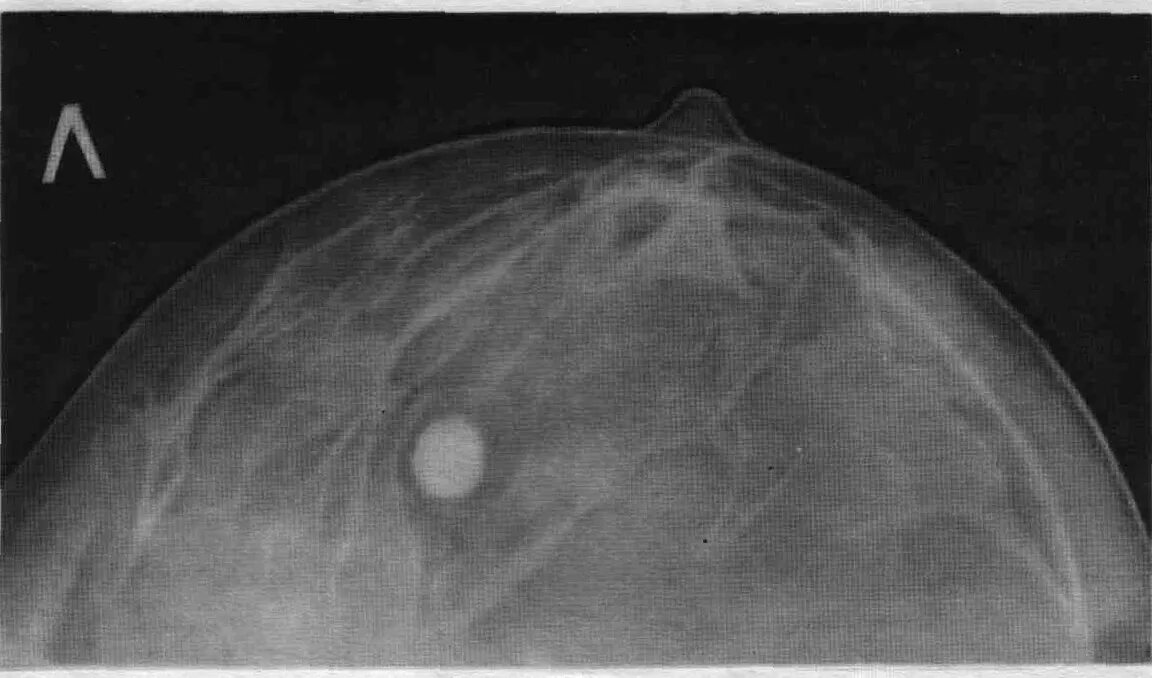

Доброкачественное новообразование молочной железы